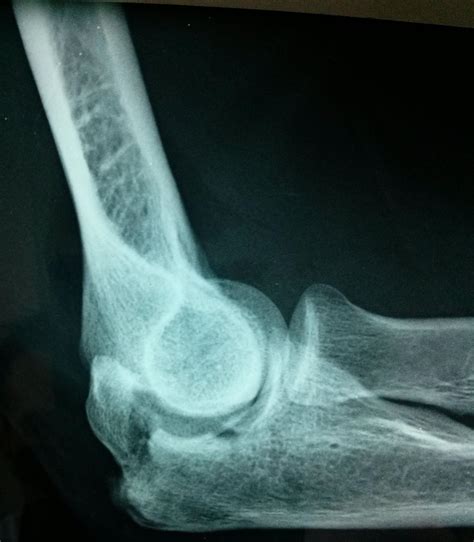

Diagnosing Elbow Hairline Fractures

Diagnosing an elbow hairline fracture typically involves a combination of physical examination and imaging tests. The diagnostic process may include:

• X-Rays: X-rays are the primary imaging tool used to diagnose hairline fractures. They can show the crack in the bone and help determine the extent of the injury.

• CT Scans: In some cases, a CT scan may be ordered to provide a more detailed view of the bone and surrounding tissues.